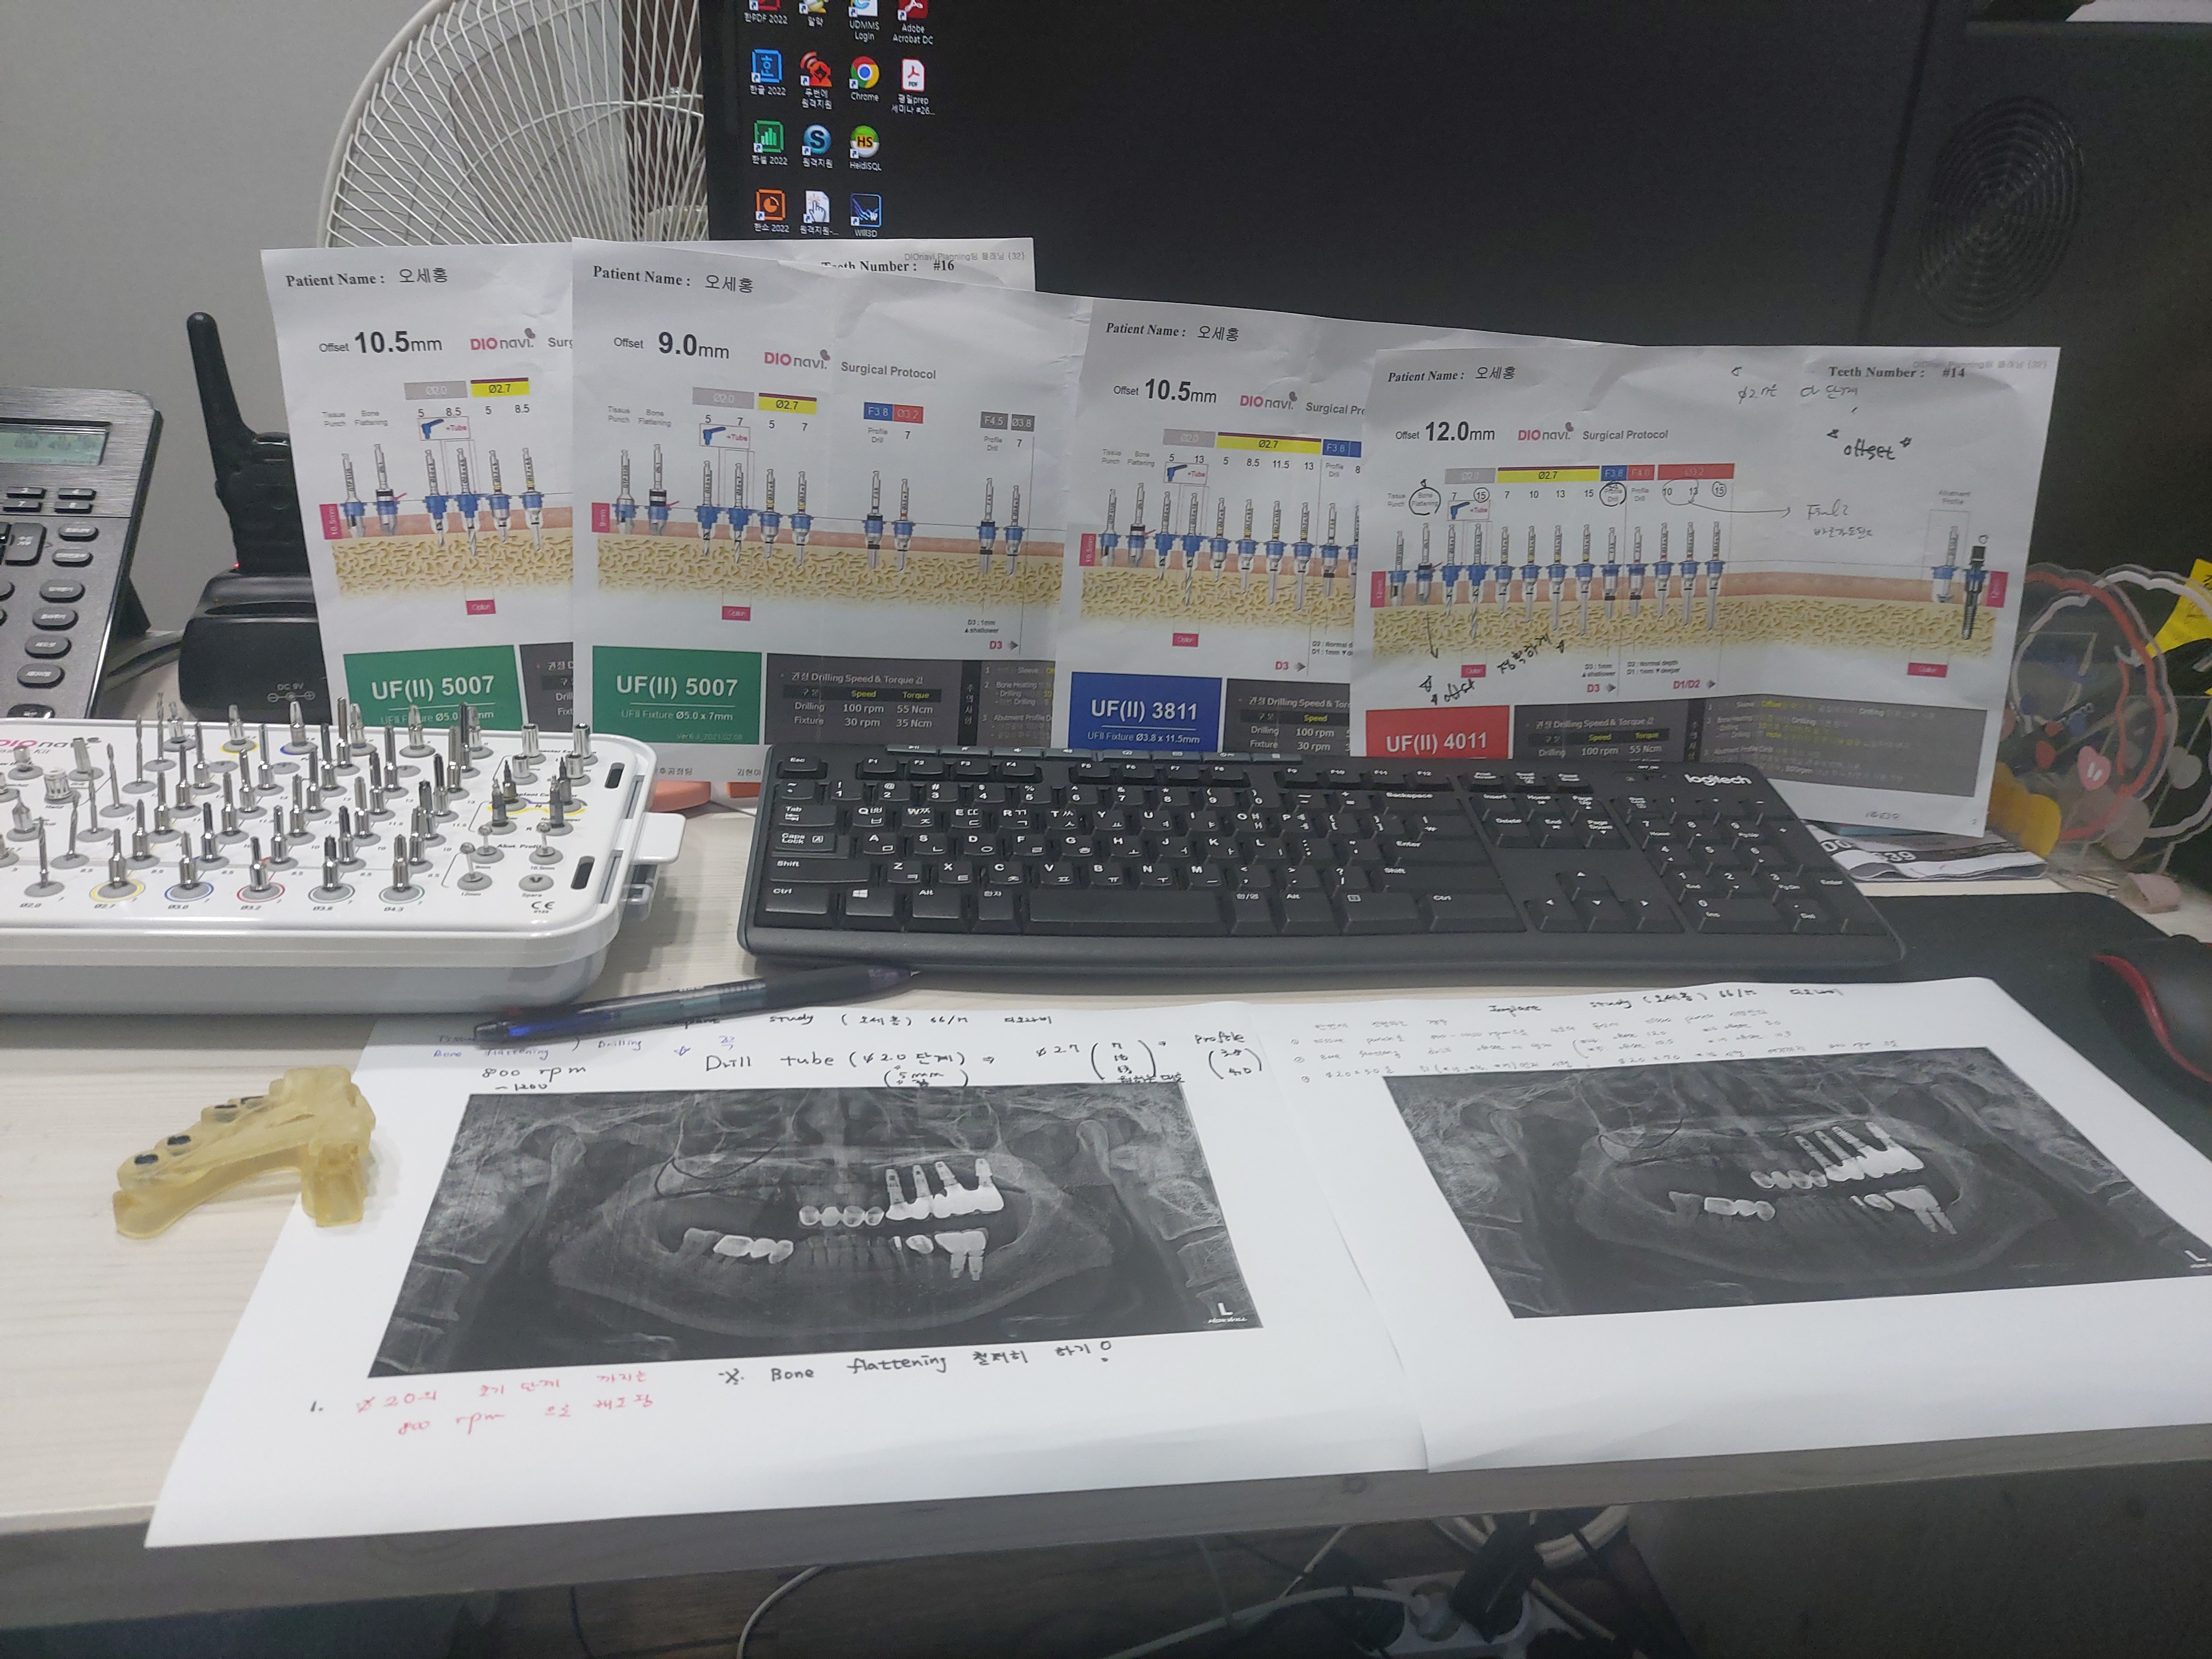

수술전 씨티와 구강스캐너를 이용하여

미리 모의 수술을 진행한 스텐트를 가지고 임플란트를 식립하는 네비게이션 임플란트 입니다.

또한 수술시 3차원적으로 계획된 스텐트를 가지고

아직 네비게이션 수술에 많은 경험이 없기에

최대한 스터디를 준비해서 진행했구요.

실제 수술이다 생각하고

실제 수술 킷트로 수차례 모의 수술을 진행하였습니다.

모의 수술중 의문 사항은 디오 임플란트 본사 담당자와 원활히 소통 하였고

늦은 시간까지 정성있는 답변에

프로의 향기를 느낄 수 있었습니다.